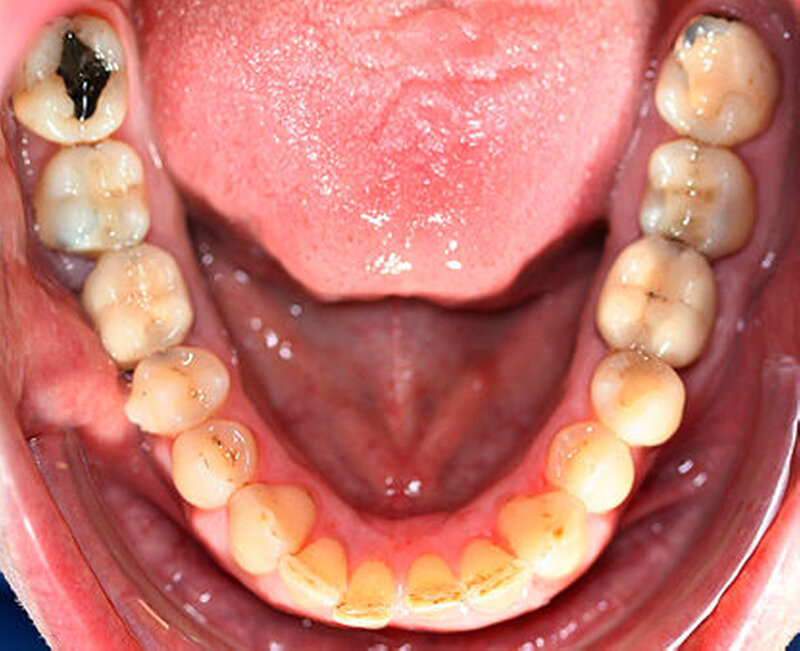

Anamnestisch lagen keine Besonderheiten vor. Es ist jedoch zu vermerken, dass ein regelmäßiger Alkohol-, Koffein- und Nikotinkonsum zugrunde lag. Intraoral zeigte sich ein bereits konservierend versorgtes permanentes Gebiss mit aktivem und inaktivem kariösen Geschehen. Große Anteile der Zahnhälse lagen nach Zahnfleischrückgang in Kombination mit Knocheneinbrüchen frei. Zahn 27 wurde bereits extrahiert.

Röntgenologisch stellte sich im Orthopantomogramm der bereits intraoral ersichtliche horizontale und vertikale Knochenabbau mit Attachmentverlust an einzelnen Zähnen dar. Die Erhaltungswürdigkeit einzelner Zähne war aufgrund des starken Knochenverlustes beziehungsweise der Beeinträchtigung des Halteapparates als kritisch zu beurteilen.

Zudem wurde die Diagnose einer Parodontitis gestellt, die eine Rücküberweisung an den Hauszahnarzt erforderlich machte (Abbildung 2).